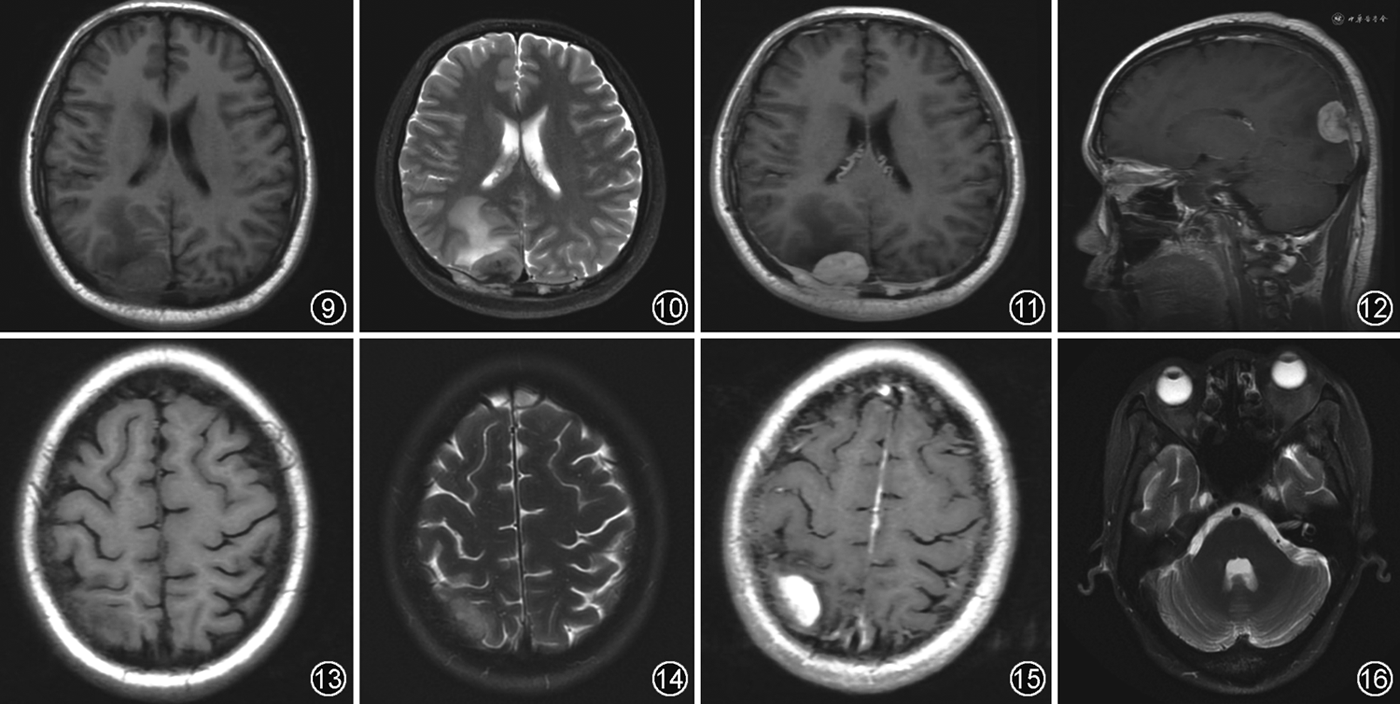

RDD累及硬脑膜时常好发于大脑凸面、海绵窦、鞍上和岩斜区等部位[11,16],少部分可表现为柔脑膜、鞍区及脑实质等部位受累[17]。病灶在T1WI呈等信号,在T2WI、DWI均呈低信号(图9~12),伴病灶周围脑实质明显水肿[16,18, 19],增强后表现为均匀强化伴硬膜尾征,少数病灶边缘可出现沿脑沟向脑实质内延伸的“伪足样”改变,提示柔脑膜受累[17]。RDD还可累及全身骨骼表现为多中心溶骨性骨质破坏[20]。

ECD常累及大脑镰、小脑幕及蝶鞍等硬脑膜。在T1WI呈等信号,T2WI呈等或低信号,增强后明显均匀强化[12,21, 22](图13~15)。ECD还可累及脑实质引起小脑综合征和锥体综合征等症状,有时还因肿块压迫导致梗阻性脑积水[23]。脑实质受累常见于幕下脑组织(如小脑齿状核及脑桥),一般表现为结节或肿块,呈双侧对称性T1WI低信号、T2WI高信号,增强后强化程度不一,大部分病灶可见强化,且病灶周围常无水肿。当累及下丘脑-垂体轴时,可出现中枢性尿崩症等症状。此外,ECD可累及颅面部骨骼或眼眶而表现为窦壁骨质增生硬化或眶内肿块[7,12,22](图16),而RDD一般为溶骨性破坏,且无眶内受累。